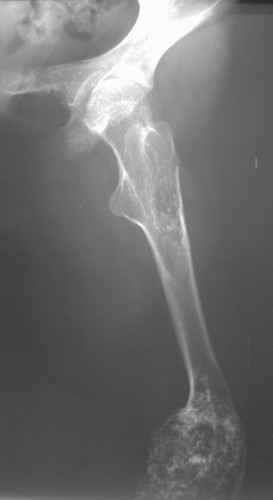

Диагноз: Дисхондроплазия. Варусная деформация дистального метафиза правой бедренной кости; состояние после оперативных вмешательств (1993 и1994 гг.).

Деформация правой нижней конечности с 6 месяцев (стала прогрессировать после года, с момента начала ходьбы). Поставлен диагноз болезнь Олье, варусная деформация, укорочение правой нижней конечности на 4,5 см. 1993 г. - операция остеоклазия на уровне очагов поражения в н/3 правой бедренной кости и в/3 правой большеберцовой кости с одномоментной коррекцией деформации и фиксацией костных фрагментов спицами Киршнера.После начала статической нагрузки (1994 г.) появился рецидив деформации и укорочения. Вторая операция - ЧКО АВФ, аппарат демонтирован через 2недели в связи с развившимся на уровне стержня переломом, после чего находилась в гипсовой повязке до консолидации костных фрагментов. Далеелечилась консервативно в гипсовой повязке. Выраженная деформация и укорочение правой нижней конечности. Относительная длина бедер: справа -34 см, слева - 51 см; анатомическая длина голеней: справа - 29 см, слева - 39 см. Величина варусной деформации на уровне дистального отдела правого бедра составляет - 80 град. Амплитуда движений в коленных суставах (разгибание/сгибание ): справа - 0/0/100 град.; слева - 0/0/30 град. Отмечается боковая и ротационная нестабильность на уровне правого коленного сустава. Амплитуда движений в голеностопных суставах - в норме. Тактика лечения? Заранее благодарю! С уважением,А.В.Владзимирский

Высылаю вам фото подобной больной, у нее тоже первая попытка до меня была безуспешной.